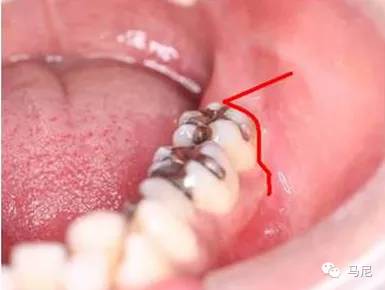

为暴露牙冠的最大周径,去骨部位和范围一般包括全部合面和部分颊侧、远中的牙槽骨质。为保持牙槽骨高度和减少去骨量,在去除颊侧及远中牙槽骨时应采用沟槽式去骨,即在患牙的颊侧和远中骨壁,紧贴患牙磨出深的沟槽,仅将与患牙紧贴的部分牙槽骨去除,这样既显露了牙冠,又达到了增隙的目的。阻生第三磨牙沟槽磨除时要注意深度、宽度和方向,沟槽的深度应达牙颈部以下,约为根长的1/3至1/2不要过深,避免损伤深面的下颌管及上颌窦等重要解剖结构;宽度约为2mm,既可容纳牙挺又不会因太宽导致牙挺失去支点在沟槽内打转;方向应与牙体、牙根的长轴平行。舌侧以及近中牙槽骨,原则上不能去除,以免损伤舌神经、邻牙及牙周骨质。总之,在微创原则指导之下,术前和术中要充分判断骨阻力的部位与大小,设计最合理的去骨和增隙方案。

此外需要提醒的是,首次去骨不宜太多,可以在分牙过程中根据实际需要再进行适当去骨。去骨仅仅需要去除覆盖牙冠的部分,颊侧及远中磨出槽沟,能放入牙挺即可。切割钻针的方向应与牙体的长轴平行,深度可达根分叉,注意不可过深以避免损伤下颌管等解剖结构。